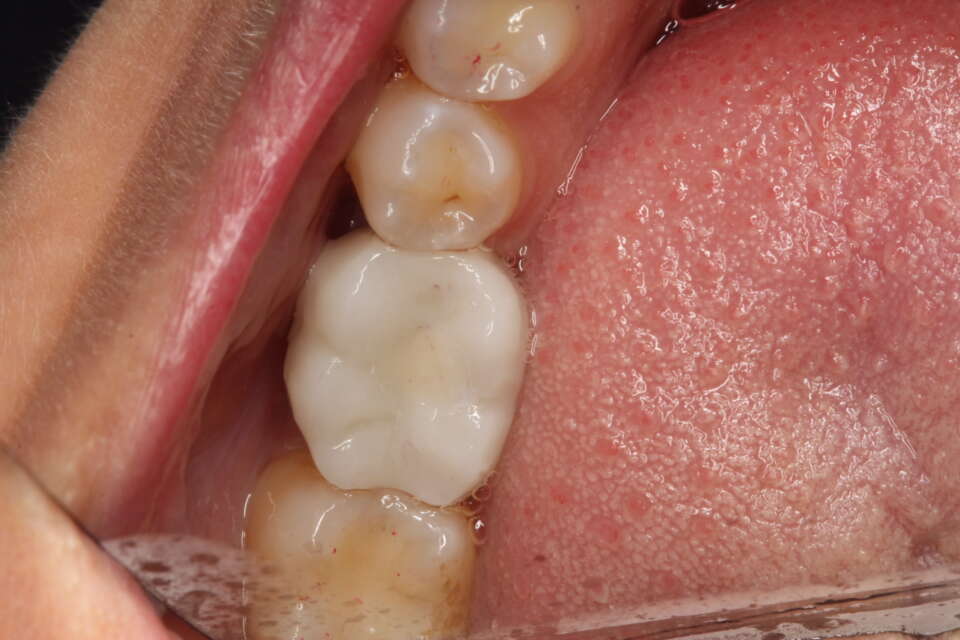

After Treatment

IMG 8705

IMG 7646

The soft tissues really like zirconia and just look how natural the new tooth looks